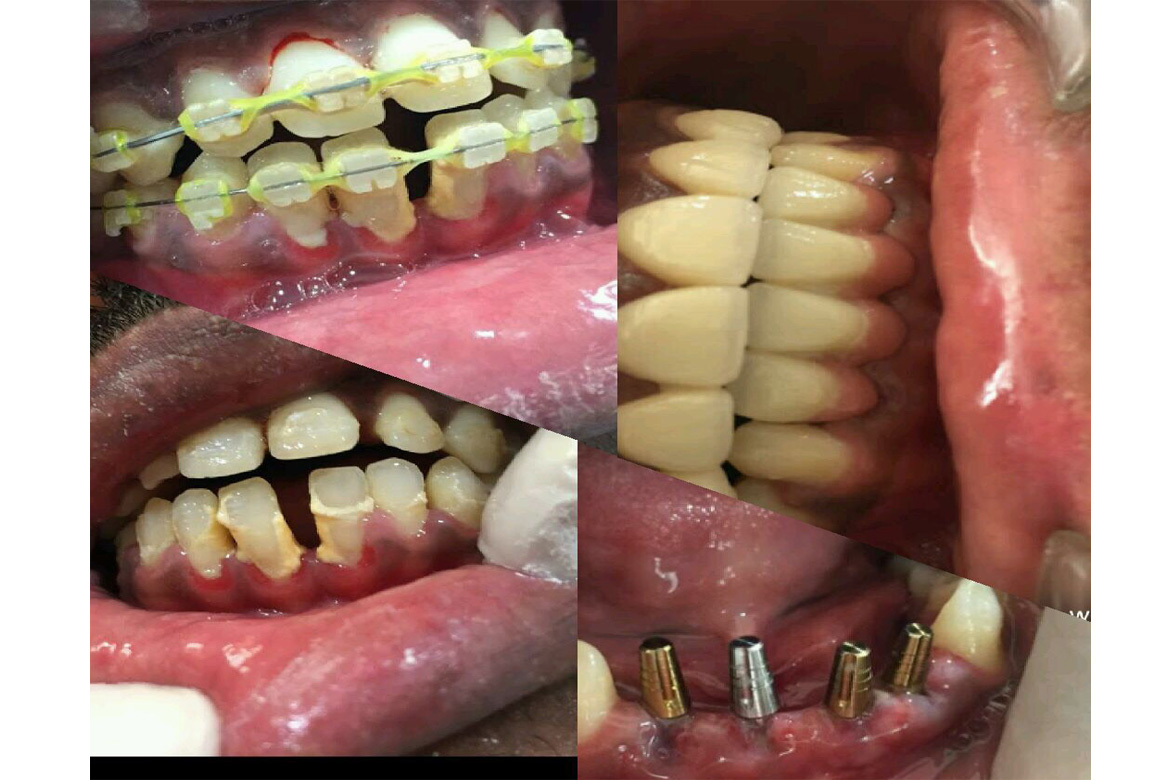

Natural teeth are devised for a life time but if u have lost your teeth for varied reasons either partially or completely or still struggling with failing teeth or traditional removable dentures then Dental Implants are a Blessing in Disguise for you.

A Dental implant is a titanium post that is placed in your jaw bone which interfaces,integrates or interlocks (as in BASAL IMPLANTS) to provide a strong and secure foundation that replaces your missing teeth permanently.

Teeth rehabilitation is very crucial as the loss of teeth will not only have an affect on the choice of food intake but also alters speech and facial contours giving the person an elderly appearance which affects their self confidence.

Although there are several forms of teeth replacement Implants are considered the best as they are durable and functionally potent.